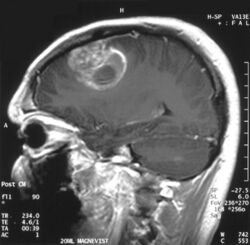

| Coronal MRI with contrast of a glioblastoma in a 15-year-old male |

Sagittal MRI with contrast of a glioblastoma WHO grade 4 in a 15-year-old boy

When viewed with MRI, glioblastomas often appear as ring-enhancing lesions. The appearance is not specific, however, as other lesions such as abscess, metastasis, tumefactive multiple sclerosis, and other entities may have a similar appearance.[59] Definitive diagnosis of a suspected GBM on CT or MRI requires a stereotactic biopsy or a craniotomy with tumor resection and pathologic confirmation. Because the tumor grade is based upon the most malignant portion of the tumor, biopsy or subtotal tumor resection can result in undergrading of the lesion. Imaging of tumor blood flow using perfusion MRI and measuring tumor metabolite concentration with MR spectroscopy may add diagnostic value to standard MRI in select cases by showing increased relative cerebral blood volume and increased choline peak, respectively, but pathology remains the gold standard for diagnosis and molecular characterization.[citation needed]